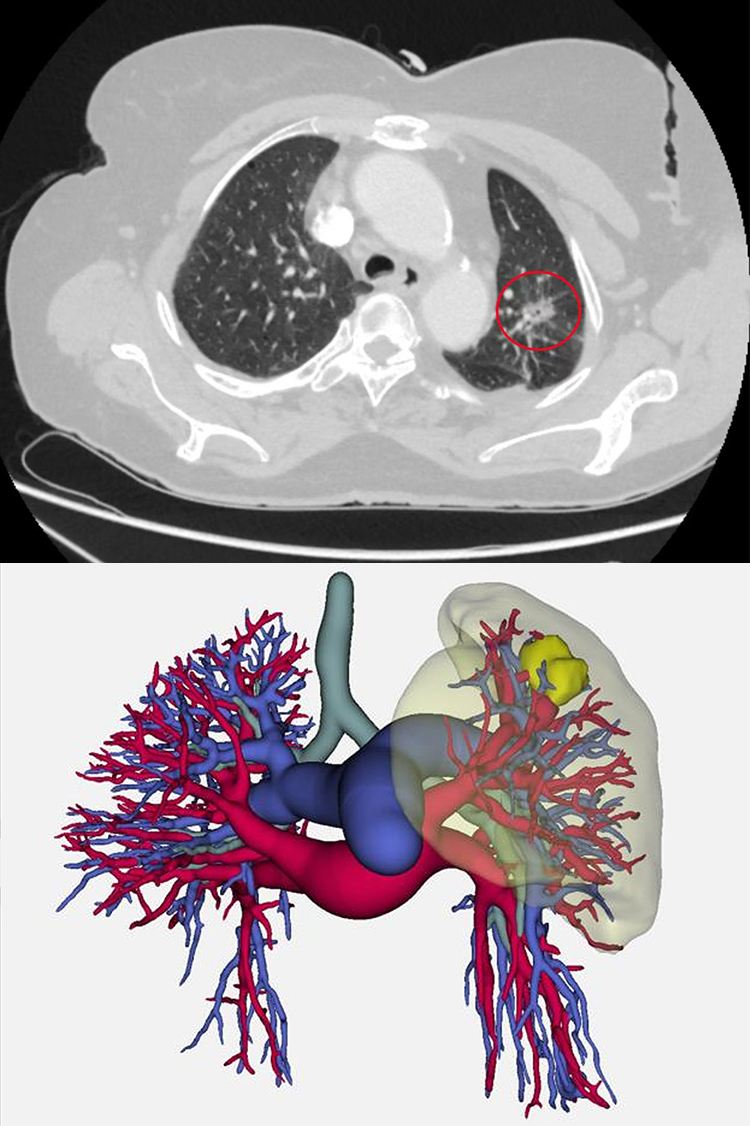

这位年过七旬的奶奶,体检时通过低剂量螺旋CT筛查发现左上肺有一个直径约2 cm的实性结节,考虑恶性肿瘤,手术指征明确。但患者同时合并有冠心病,若采用传统腔镜手术,手术创伤大、术后疼痛剧烈、恢复期长,对于年事已高的患者而言,将是不小的考验,因此,创伤更小的单孔胸腔镜手术无疑是更优选择。

“肺癌之所以可怕,往往是因为发现得太晚”。中南大学湘雅三医院冯伟医生表示:当出现刺激性咳嗽、痰中带血、胸痛等症状时,病情多已进展至中晚期,治疗难度大,预后较差,因此肺癌治疗的关键点在于早诊早治。需要首先明确高危人群,如长期吸烟或吸二手烟者、有职业暴露史(如石棉、铍、铀、氡等接触者)、有家族遗传史,以及患有慢性阻塞性肺疾病等人群,都是肺癌的重点筛查对象。他介绍:低剂量螺旋CT是目前最有效的肺癌早期筛查手段,它可以清晰地发现肺部微小结节,其辐射剂量也远低于常规CT。本次手术的患者正是通过这一技术获益的典型。其次,要正确看待肺结节,体检发现肺结节不等于罹患肺癌,大部分结节是良性的。关键在于由胸外科医生进行甄别和定期随访。对于高度可疑的结节,及时进行微创手术干预,即可达到根治效果,五年生存率可超过90%。